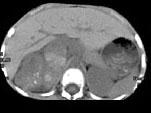

问题 男,5 岁,消瘦、贫血、纳差和腹部包块3个月,CT检查如图,下列说法正确的是 ( )

选项 A、该病灶来源于右肾上腺,考虑为神经母细胞瘤 B、该病灶来源于右肾,考虑为肾胚胎瘤 C、肿块密度不均匀,可见片状的较高密度,考虑为出血,也可见点状的钙化影 D、该病灶来源于肝脏,考虑为肝母细胞瘤 E、右侧腹腔内可见一巨大软组织肿块影,其边界欠清楚

答案 ACE